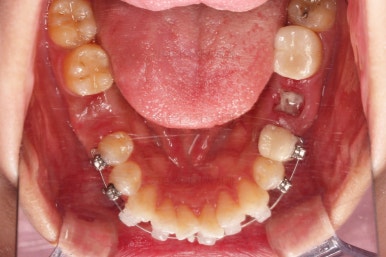

이제 미니스크류가 등장합니다.

상하좌우 발치 공간의 크기와 위치가 제각각이라서 당겨지는 양과 속도가 차이납니다.

그래서 미니스크류를 반드시 써줘야 합니다.

어느새 틈도 다 닫히고요.

마무리 과정만 남았습니다.

틈이 다 없어졌고, 교합도 양호합니다.

무엇보다 임플란트 없이 결손부위가 깔끔하게 채워졌고요.

매우 다행으로 사랑니도 다 있었기 때문에 마치 큰 어금니가 다 있는 것과 같은 상황이 되었습니다.

역설적이게도 손상된 큰 어금니가 없었던 부위는 작은 어금니를 발치함으로 인해 오히려 치아 갯수가 모자라 보이는 상황까지 왔네요.(어금니가 결손된 부분이 더 자연스럽게 보이는 상황)